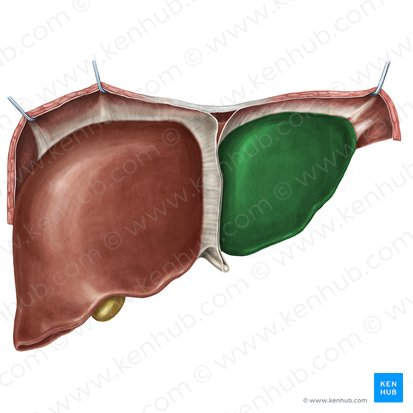

Right lobe of Liver

The larger of the two main lobes of the liver, located on the right side of the abdomen.

Left lobe of the Liver

The smaller of the two main lobes of the liver, located on the left side of the abdomen.

Falciform Ligament of the Liver

A broad, thin fold of peritoneum that attaches the liver to the anterior abdominal wall and diaphragm. It also marks the division between the right and left lobes on the anterior surface.